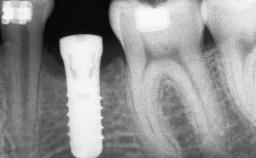

Ridge Preservation and Implant Placement for a Fixed Dental Prosthesis After a Car Accident

It is well known to clinicians that any removal of teeth will, over time, cause the dimensions of the alveolar ridge to be reduced by resorption of the bundle bone and by changes related to external modeling. This development is particularly evident in the crestal region with its thin buccal bone that consists of bundle bone almost entirely. The facial bone will rapidly resorb as blood supply from the periodontal ligament gets disrupted (Araújo and Lindhe 2005). There is no reason why traumatic tooth loss should not have the same consequences. It takes more than achieving implant osseointegration for a treatment outcome to be considered successful. No deficiency of bone or soft tissue is acceptable when an ideal esthetic outcome is the goal. Several articles (Sanz and coworkers 2011; Vignoletti and coworkers 2011) have reported on techniques of improving the alveolar ridge for implant treatment, notably focusing on protecting tissues from resorption.

# of Implants 4

Type of Implants One-Piece|Reduced-Diameter

Bone Volume Deficient vertically or deficient vertically AND horizontally